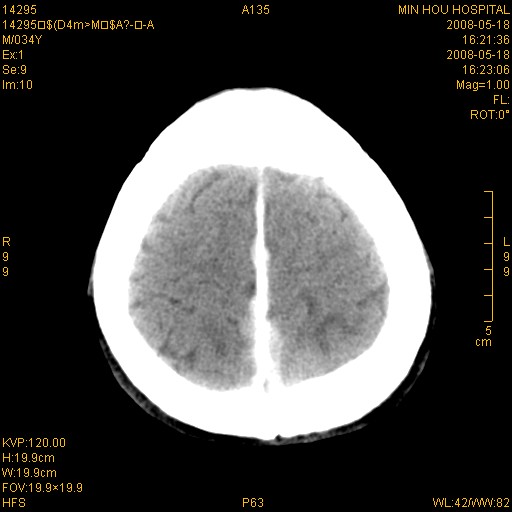

标题: CT13617:双顶叶白质水肿伴大脑镰小脑幕广泛钙化 [打印本页]

标题: CT13617:双顶叶白质水肿伴大脑镰小脑幕广泛钙化

双侧侧脑室后脚旁对称性低密度影,符合肾上腺白质营养不良(成人型)改变    小脑幕及大脑廉钙化  可考虑为生理性

支持:1、肾上腺白质营养不良.2、小脑幕、大脑镰广泛钙化。3、建议进一步检查。

硬脑膜钙化是主因,双侧顶叶白质密度减低是可能由于静脉路回流受阻所致。